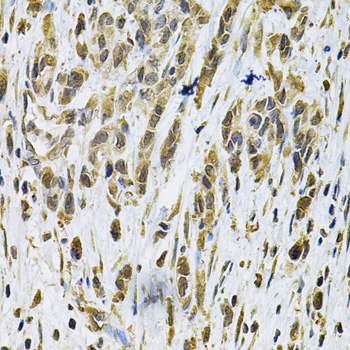

Immunohistochemistry of paraffin-embedded rat brain using RhoA at dilution of 1:100 (40x lens).

Immunohistochemistry of paraffin-embedded human gastric cancer using RhoA at dilution of 1:100 (40x lens).

Immunohistochemistry of paraffin-embedded mouse brain using RhoA at dilution of 1:100 (40x lens).

IHC 1:50 - 1:200